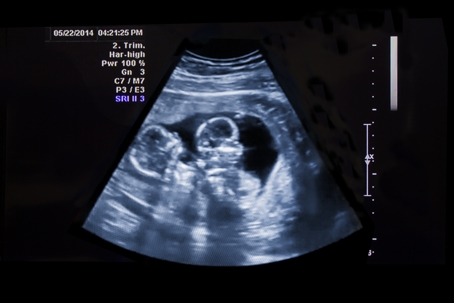

Twins Ultrasound

Twin-to-Twin Transfusion Syndrome (TTTS) is a rare but serious medical condition that affects identical twins who share a single placenta. The condition occurs in about 10–15% of monochorionic twins, where an imbalance in the blood supply develops between the two fetuses. TTTS can have life-threatening implications for both twins if not detected and treated.

Early and accurate diagnosis of Twin-to-Twin Transfusion Syndrome (TTTS) is crucial for ensuring the well-being of both twins. Typically, TTTS can be detected as early as 16 weeks into pregnancy through routine ultrasound examinations, which play a significant role in assessing the twins' development. Prenatal care providers focus on spotting the key indicators associated with TTTS.